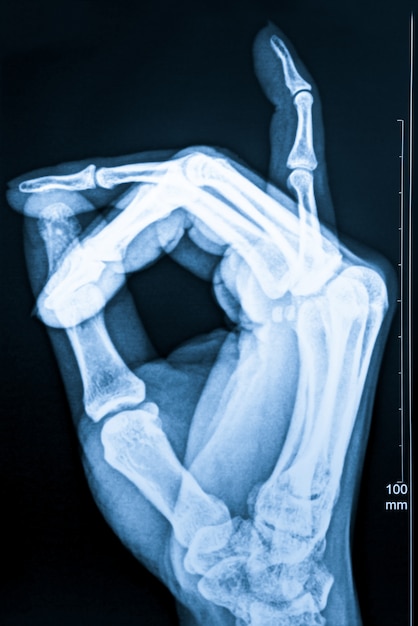

Cechy charakterystyczne raka kości, które można dostrzec na zdjęciach RTG, obejmują różnorodne zmiany destrukcyjne. Przede wszystkim zauważalne są obszary osteolityczne, co oznacza uszkodzenie tkanki kostnej. Te zmiany często mają nieregularne kształty, co sprawia, że trudno je odróżnić od zdrowej tkanki. Ważnym sygnałem wskazującym na obecność nowotworu kości jest również przerwanie ciągłości kości.

Na zdjęciu RTG można również dostrzec odczyny okostnej, takie jak:

- trójkąt Codmana,

- „spikule” kostne.

Te struktury mogą sugerować agresywny charakter nowotworu. Ponadto, naciekanie tkanek miękkich często objawia się jako zacienienie w okolicy guza, co dodatkowo podkreśla obecność patologicznych zmian.

Interpretacja zdjęć RTG w kontekście raka kości to zadanie wymagające dokładnej analizy cech, które mogą sugerować obecność nowotworu. Lekarze koncentrują się na zmianach destrukcyjnych, takich jak obszary osteolityczne, które mogą wskazywać na uszkodzenie tkanki kostnej. Charakteryzują się one często nieregularnymi granicami, co sprawia, że trudno je odróżnić od zdrowych tkanek.

Istotnym sygnałem wskazującym na zaawansowany proces chorobowy jest przerwanie ciągłości kości. Specjaliści przyglądają się także odczynom okostnej, w tym trójkątowi Codmana, który może sugerować agresywny charakter nowotworu. Obecność tych odczynów oraz ewentualne nacieki tkanek miękkich podkreślają, jak ważna jest szczegółowa analiza zdjęć RTG.